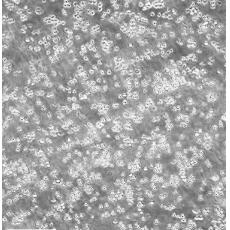

MOLT-4

中文名稱 人急性淋巴母細胞白血病細胞

組織來源 急性T淋巴細胞白血??;男性

生長特性 suspension

形態(tài)特征 lymphoblast

細胞描述 MOLT-4與MOLT-3來源于一名19歲的男性急性淋巴細胞性白血病的復發(fā)患者,該患者前期接受過多種藥物聯(lián)合化療。MOLT-4細胞系為T淋巴細胞起源,p53基因的第248位密碼子有一個G→A突變,不表達p53,不表達免疫球蛋白或EB病毒;可產(chǎn)生高水平的末端脫氧核糖轉(zhuǎn)移酶;表達CD1(49%),CD2(35%),CD3A(26%)B(33%)C(34%),CD4(55%),CD5(72%),CD6(22%),CD7(77%)。